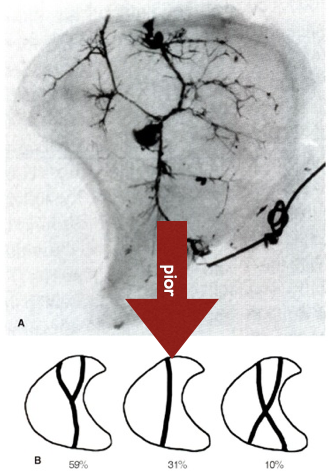

Vascularização do Semilunar

Kienbock